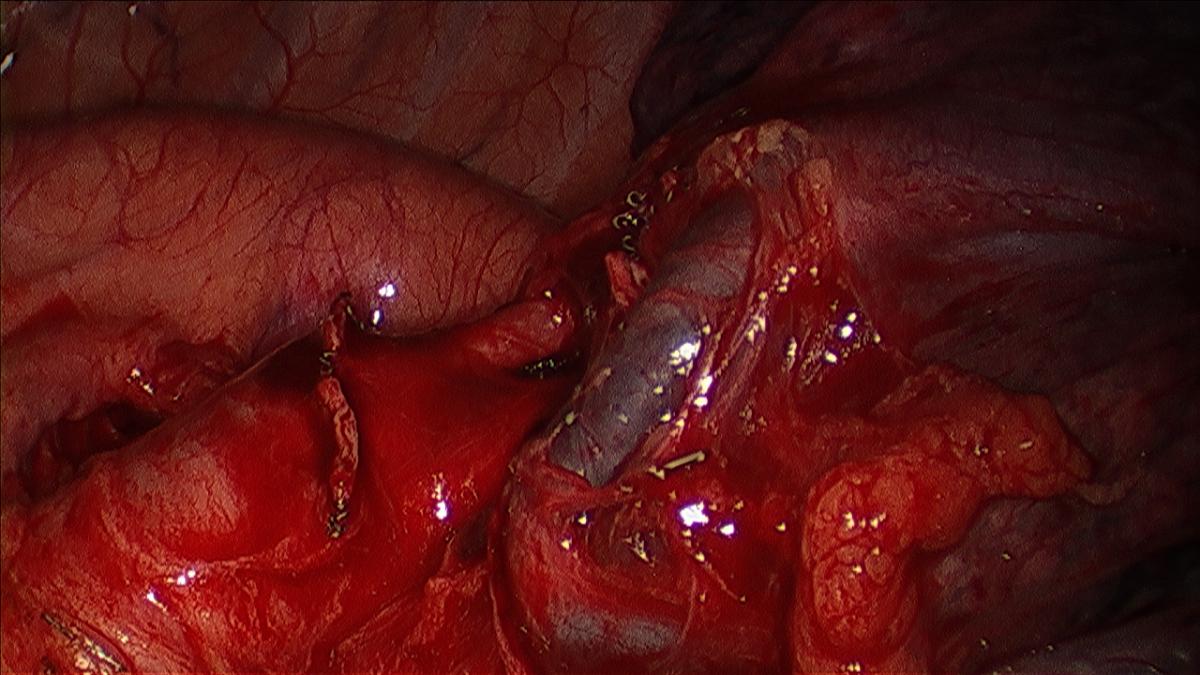

Figure 2: Dissected apical tri-segment and lingular vein.

The camera is switched back to the anterior incision, the table rolled posteriorly, and the upper lobe retracted posteriorly. The superior pulmonary vein is dissected sharply and bluntly (sucker or peanut) circumferentially and distally until the trunk of the apical tri-segments and the lingular veins are clearly identified (Figure 3). Circumferential Isolation of the tri-segmental vein is done using a thoracoscopic right angle through the working incision, or by passage of a thoracoscopic curved vascular clamp via the posterior incision (Videos 1, 2).